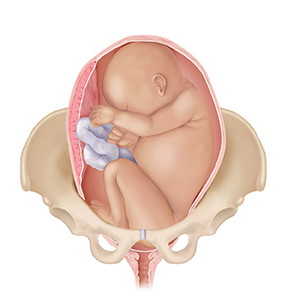

A baby (the fetus) often moves down between the pelvic bones (descend) before birth. If this is your first pregnancy, this may happen 2 to 4 weeks before labor. With repeat pregnancies, the baby may not “drop” until labor begins. The baby usually moves down headfirst. If your baby is not in a safe position for birth, or if there is a problem with the placenta, you may need special care. A cesarean section delivery may be needed.

Transverse position.Baby lies horizontally across the pelvis.